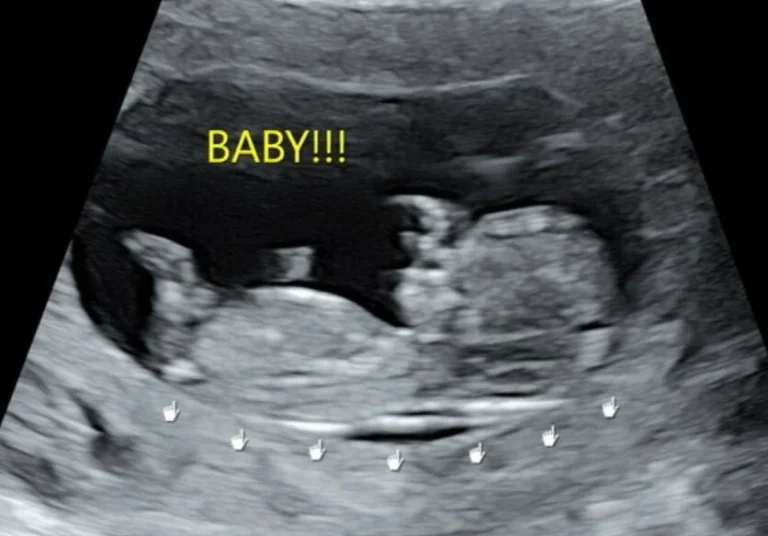

“Today I was visited by Jan and her daughter Amy, a 13year old in 4th Primary school. Jan has seen concerning changes in her daughter that prompted her to bring the daughter to me for medical help. I discovered Amy is 1 month pregnant. Both the mother and her daughter were taken back and are heart broken. The shocking news caused them a lot of worry and stress. Because I am pro-life, I have given both the mother and her daughter counseling in hopes she chooses life for this growing baby. But the mother’s decision is still pending as she can’t decide and now she is speechless. We Pray that God intervenes in this situation for the power and grace belongs to him. Thank you!”